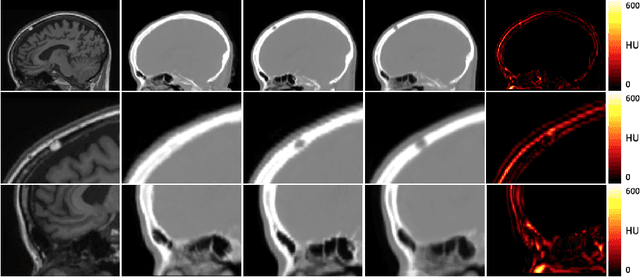

Abstract:The ability to synthesise Computed Tomography images - commonly known as pseudo CT, or pCT - from MRI input data is commonly assessed using an intensity-wise similarity, such as an L2-norm between the ground truth CT and the pCT. However, given that the ultimate purpose is often to use the pCT as an attenuation map ($\mu$-map) in Positron Emission Tomography Magnetic Resonance Imaging (PET/MRI), minimising the error between pCT and CT is not necessarily optimal. The main objective should be to predict a pCT that, when used as $\mu$-map, reconstructs a pseudo PET (pPET) which is as close as possible to the gold standard PET. To this end, we propose a novel multi-hypothesis deep learning framework that generates pCTs by minimising a combination of the pixel-wise error between pCT and CT and a proposed metric-loss that itself is represented by a convolutional neural network (CNN) and aims to minimise subsequent PET residuals. The model is trained on a database of 400 paired MR/CT/PET image slices. Quantitative results show that the network generates pCTs that seem less accurate when evaluating the Mean Absolute Error on the pCT (69.68HU) compared to a baseline CNN (66.25HU), but lead to significant improvement in the PET reconstruction - 115a.u. compared to baseline 140a.u.

Abstract:Attenuation correction is an essential requirement of positron emission tomography (PET) image reconstruction to allow for accurate quantification. However, attenuation correction is particularly challenging for PET-MRI as neither PET nor magnetic resonance imaging (MRI) can directly image tissue attenuation properties. MRI-based computed tomography (CT) synthesis has been proposed as an alternative to physics based and segmentation-based approaches that assign a population-based tissue density value in order to generate an attenuation map. We propose a novel deep fully convolutional neural network that generates synthetic CTs in a recursive manner by gradually reducing the residuals of the previous network, increasing the overall accuracy and generalisability, while keeping the number of trainable parameters within reasonable limits. The model is trained on a database of 20 pre-acquired MRI/CT pairs and a four-fold random bootstrapped validation with a 80:20 split is performed. Quantitative results show that the proposed framework outperforms a state-of-the-art atlas-based approach decreasing the Mean Absolute Error (MAE) from 131HU to 68HU for the synthetic CTs and reducing the PET reconstruction error from 14.3% to 7.2%.